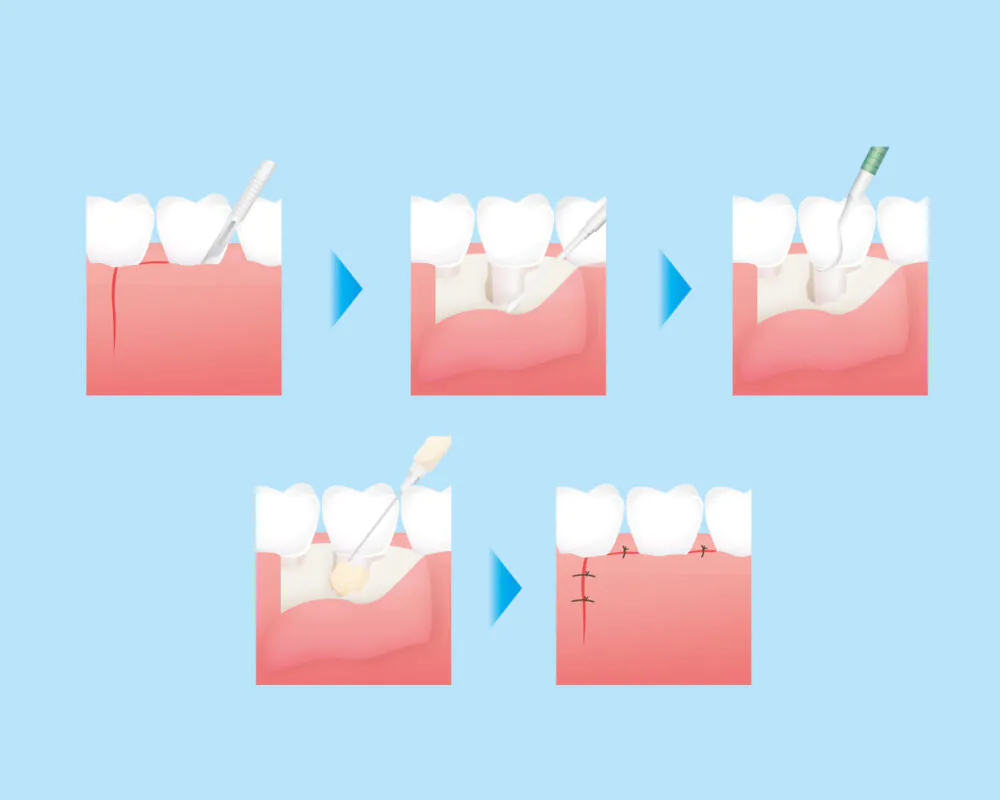

フラップ手術

フラップ手術は、深刻な歯周ポケットが存在する場合に実施されます。この手術では、歯肉を切開し、歯周ポケットの奥深くに蓄積した歯石を取り除きます。目視で歯石を確認でき、徹底的な清掃が可能となります。また、感染している歯肉を取り除くなどの処置を行います。

フラップ手術は、深刻な歯周ポケットが存在する場合に実施されます。この手術では、歯肉を切開し、歯周ポケットの奥深くに蓄積した歯石を取り除きます。目視で歯石を確認でき、徹底的な清掃が可能となります。また、感染している歯肉を取り除くなどの処置を行います。